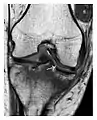

The diagnostic performance of MRI in the detection of occult fractures has been shown to be comparable, or better than MDCT. Indeed, while the specificity of both CT and MRI for the diagnosis of fracture can be as high as 100%, the sensitivity was reported to be higher for MRI. The superiority of MRI over any other imaging modality including MDCT for the detection of occult hip fractures is now recognised. For instance, an occult intertrochanteric extension of a greater trochanter fracture can be most effectively appreciated on MRI Moreover, MRI is extremely helpful in detecting associated soft tissue abnormalities, especially ligamentous lesions. MRI is now considered as the standard in this context. However, because of its relative unavailability in emergency settings and high costs, MRI may only be performed in "high risk patients" with negative X-rays. For example, when a hip occult fracture is suspected, patients with reduced baseline mobility and pain on axial compression are considered at risk and, therefore, should be examined by MRI. MRI signs of occult fractures are evident several weeks before radiographic signs appear. In the hip, a limited and cost-effective MR protocol, with only T1 weighted () coronal images, may enable a reliable diagnosis or exclusion of occult fracture in very little time, for example, 7 minutes. Typically, a linear hypointensity is observed on T1 W images. MRI is also highly sensitive to marrow abnormalities surrounding the fracture line, which appear as hypointensity on T1 W images and hyperintensity on fluid-sensitive sequences. Such signal changes are thought to be a combination of bone marrow edema, intraosseous haemorrhage, and/or granulation tissue and help to identify even undisplaced fractures. However, in the absence of a history of trauma and linear hypointensities on T1 W images, isolated bone marrow edema may represent other pathologies such as osteoid osteoma and sclerosing osteomyelitis.[1]

Figure 1: A 56-year-old woman presenting with left knee pain after a fall. (a) Initial anteroposterior radiograph was considered normal, however, subtle cortical disruption of the anterior rim of the medial tibial plateau, medial to the tibial spine, is noted (arrow). (b) Coronal T1-weighted MRI confirms the cortical disruption (arrow) and shows extensive fracture through the proximal tibia. (c) Coronal proton density-weighted image with fat saturation shows extensive edema in the subchondral bone. Note also hypersignal adjacent to the medial collateral ligament corresponding to a grade I sprain (arrowheads).[1]